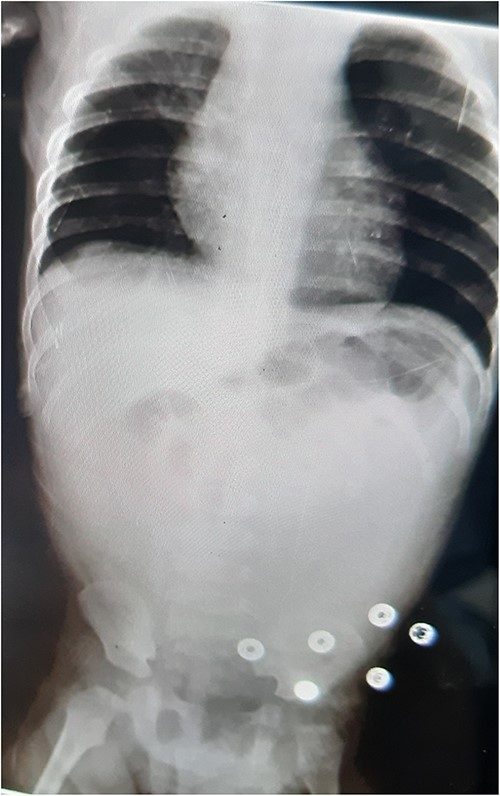

An abdominal X-ray revealed no gas liquid levels or free gas in the abdomen. Intestinal loops were dilated, and there was a lack of gas in the abdomen and pelvis. Twelve hours later, the patient developed severe abdominal pain with generalized abdominal guarding. The hemoglobin level dropped to 6.8, necessitating an emergency exploratory laparotomy (Fig. 1).

AXR: no gas liquid levels—no free gas in the abdomen—dilation of intestinal loops and lack of gas in the abdomen and pelvis.